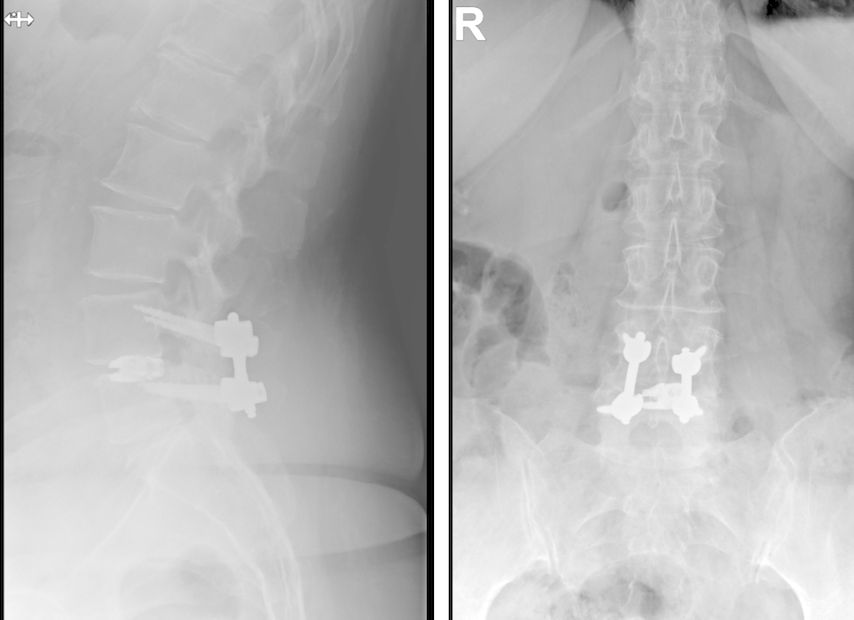

Fallbeispiel 1

Beispiel für die Implantation zervikaler Pedikelschrauben. In diesem Fall kam es bei einem 61-jährigen Patienten 10 Jahre nach anteriorer zervikaler Diskektomie und Fusion (ACDF) C4/5 und ventraler Verplattung C4–6 zu einer Ankylosierung auch von C6/7. Nach Sturz kam es zu einer Fraktur bei C6/7 mit begleitender Bogenfraktur und auch Beteiligung der dorsalen Ligamenta (Abb. 1 und 2). Klinisch bestanden ausgeprägte Nackenschmerzen und kein neurologisches Defizit. Es wurde die Indikation der dorsalen Verschraubung von C4 auf Th1 gestellt. Intraoperativ wurde routinemäßig zusätzlich eine kleine Referenzschraube in einer Lamina – entfernt von der Dornfortsatz-Referenzklemme für die Navigation – gesetzt. Mit dieser konnte intraoperativ die Genauigkeit der Navigation exakt überprüft werden (Abb. 4 und 5). Mittels navigierter High-Speed-Fräse wurden die Schraubenkanäle vorgebohrt (Abb. 6), im Anschluss wurde der Bohrkanal ausgetastet und die Schrauben wurden implantiert. Abbildung 7 zeigt eine Röntgenkontrolle 3 Monate postoperativ.